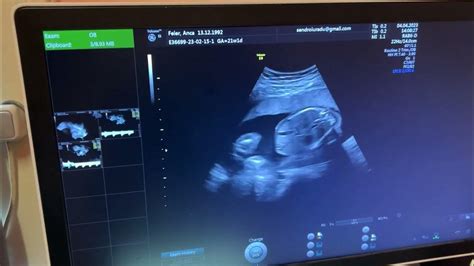

Pe măsură ce embrionul continuă să crească, sistemul nervos, creierul și măduva spinării încep să se contureze. Ulterior, se dezvoltă sistemul digestiv, rinichii, plămânii și sistemul genital, iar primele trăsături ale bebelușului devin vizibile la ecografie.

Continuă modificările fizice și psihice ale mamei, pe măsură ce fătul crește și devine mai puternic. Burtica devine mai vizibilă, iar mama își poate desfășura activitățile zilnice. În această perioadă, se poate afla sexul copilului. Este importantă monitorizarea atentă și prezentarea la medic la primele semne de contracții susținute, sângerări sau dureri abdominale.

Apropierea momentului nașterii aduce bucurie, dar și un disconfort fizic mai accentuat. Fătul crește și este mai agitat, iar mișcările pot fi mai limitate. Este necesară efectuarea unui nou set de analize medicale. Se discută despre morfologia fetală de trimestru 2, un test imagistic important pentru evaluarea dezvoltării bebelușului.